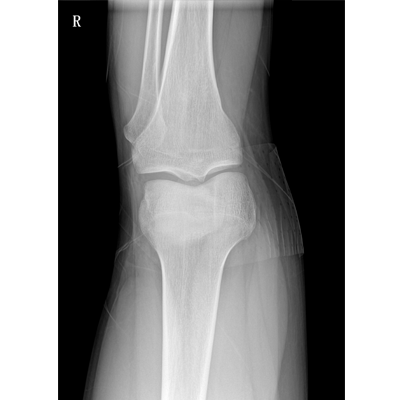

用于影像科、急診室、病房、ICU、手術(shù)室等多場(chǎng)景應(yīng)用。

● 數(shù)字化無線平板成像,操作簡(jiǎn)便,成像質(zhì)量高